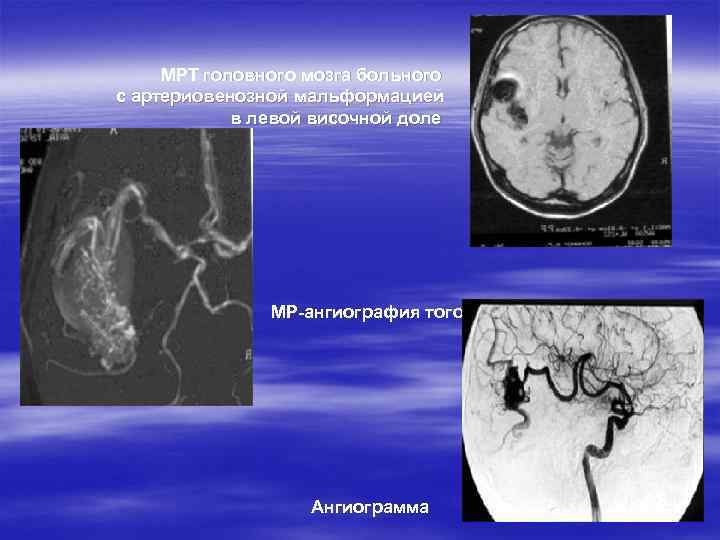

ДИАГНОСТИКА АРТЕРИО-ВЕНОЗНЫХ МАЛЬФОРМАЦИЙ § § § Оценка жалоб Анализ анамнеза заболевания Оценка неврологического статуса МРТ, МР ангиография, 3 -D КТ Ангиография

МРТ головного мозга больного с артериовенозной мальформацией в левой височной доле МР-ангиография того- же больного Ангиограмма